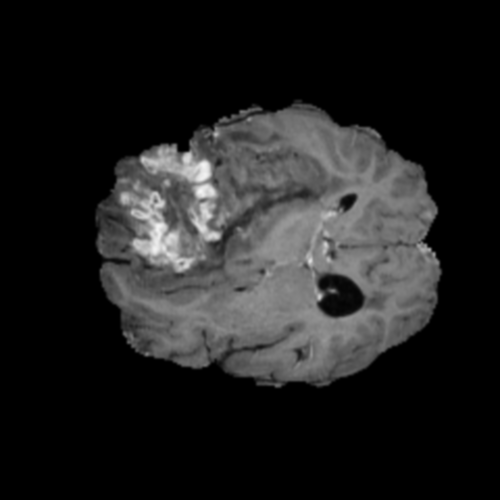

Ejemplos de Modalidades MRI

Visualización de las 4 modalidades de resonancia magnética y las segmentaciones de zonas tumorales utilizadas para entrenar el modelo

Glioma de Alto Grado (HGG)

FLAIR HGG

FLAIR

T1ce HGG

T1ce

T2 HGG

T2

T1 HGG

T1

Núcleo HGG

Núcleo

Edema HGG

Edema

Realce HGG

Realce

Tumor Completo HGG

Tumor Completo

Núcleo Edema Realce

📊 Modalidades de MRI Utilizadas

• T1: Secuencia ponderada en T1, proporciona gran detalle anatómico con líquidos oscuros

• T1ce: T1 con realce de contraste (Gadolinio), ilumina partes activas del tumor con barrera hematoencefálica comprometida

• T2: Secuencia ponderada en T2, sensible a patologías donde líquidos aparecen brillantes

• FLAIR: Recuperación de inversión atenuada en fluidos, similar a T2 pero suprime señal de LCR para visualizar edema peritumoral